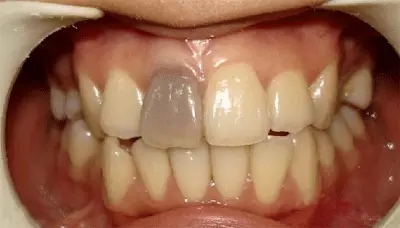

死髓牙

PS:传统的根管治疗仅靠医生经验操作,难以保留未受感染的牙髓,也不能一次性成功完成根管治疗,基本根管治疗后的牙齿都是死髓牙了。